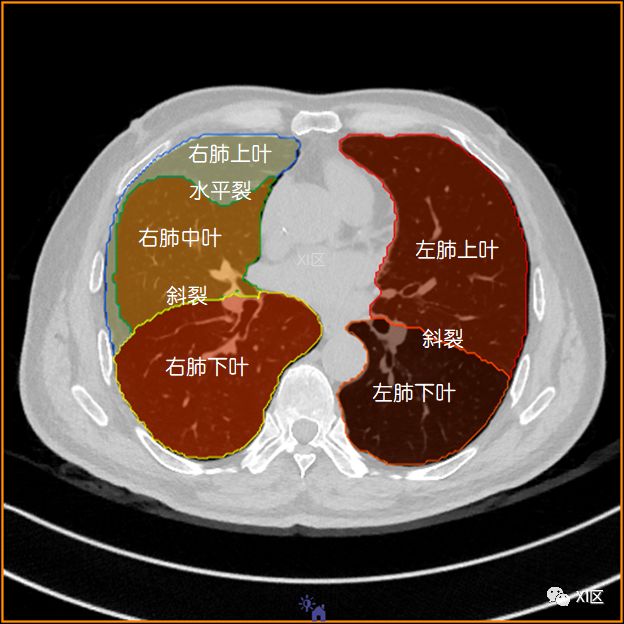

肺的分叶

左肺借斜裂成上、下两叶;右肺借斜裂和水平裂成上、中和下叶三叶。

横断位